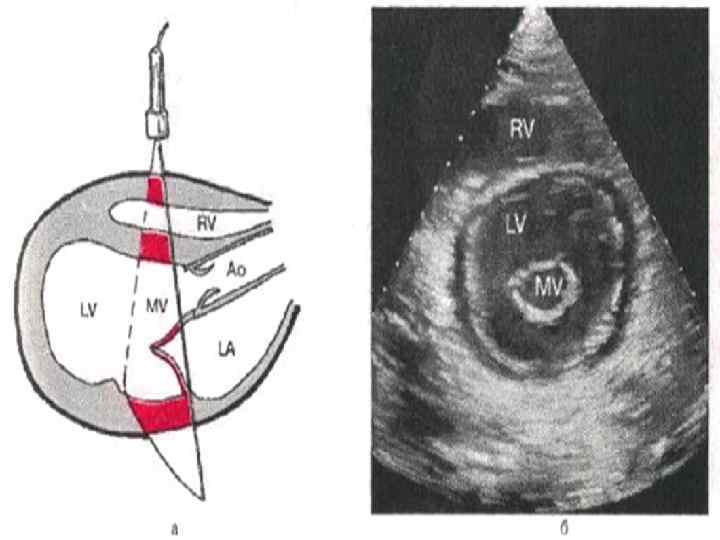

Ультразвуковая анатомия сердца В эхокардиографии используют ряд доступов к сердцу и магистральным сосудам: • Левый парастернальный • Апикальный • Субкостальный • Супрастернальный • Правый парастернальный

ОЦЕНКА НАРУШЕНИЙ РЕГИОНАЛЬНОЙ СОКРАТИМОСТИ ЛЕВОГО ЖЕЛУДОЧКА Выявление локальных нарушений сократимости ЛЖ с помощью двухмерной эхокардиографии имеет важное значение для диагностики ИБС. Исследование обычно проводится из верхушечного доступа по длинной оси в проекции двух и четырехкамерного сердца, а также из ле вого парастернального доступа подлинной и короткой осям. В соответствии с рекомендациями Американской ассоциации эхокардиографии ЛЖ при этом условно делится на 16 сегментов, располагающихся в плоскости трех поперечных сечений сердца, зарегистрированных из левого парастернального доступа по короткой оси. Изображение 6 ти базальных сегментов — переднего (А), переднеперегородочного (AS), задне перегородочного (IS), заднего (I), заднебокового (IL) и переднебокового (AL), — получают при локации на уровне створок митрального клапана (SAX MV), а средних частей тех же 6 ти сегмен тов — на уровне тапиллярных мышц (SAX PL). Изображения 4 верхушечных сегментов перед него (А), перегородочного (S), заднего (I) и бокового (L), — получают при локации из парастер нальногодоступа на уровне верхушки сердца (SAX АР).